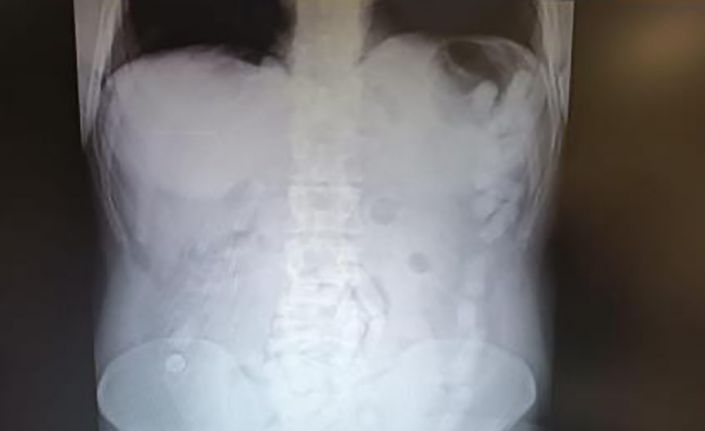

4 Mayıs 2024’te Kayseri İl Emniyet Müdürlüğü Narkotik Suçlarla Mücadele Şube Müdürlüğü ekipleri, yabancı uyruklu A.H.’nin ülkeye giriş yaparak üzerindeki uyuşturucu maddeleri Kayseri’ye getireceğini tespit etti. Şahsı takibe alan ekipler, yerini tespit ettikten sonra operasyon düzenledi. Kayseri Şehir Hastanesinde ultrason çekimi ile yapılan kontrolde şahsın midesinde çok sayıda kapsül olduğu tespit edildi. Yapılan operasyonla şahsın midesinden çıkarılan 100 adet kapsülün içerisinde 729 gram uyuşturucu madde ele geçirildi. İşlemlerinin ardından adliyeye sevk edilen şüpheli, çıkarıldığı mahkemece tutuklanarak cezaevine gönderildi.